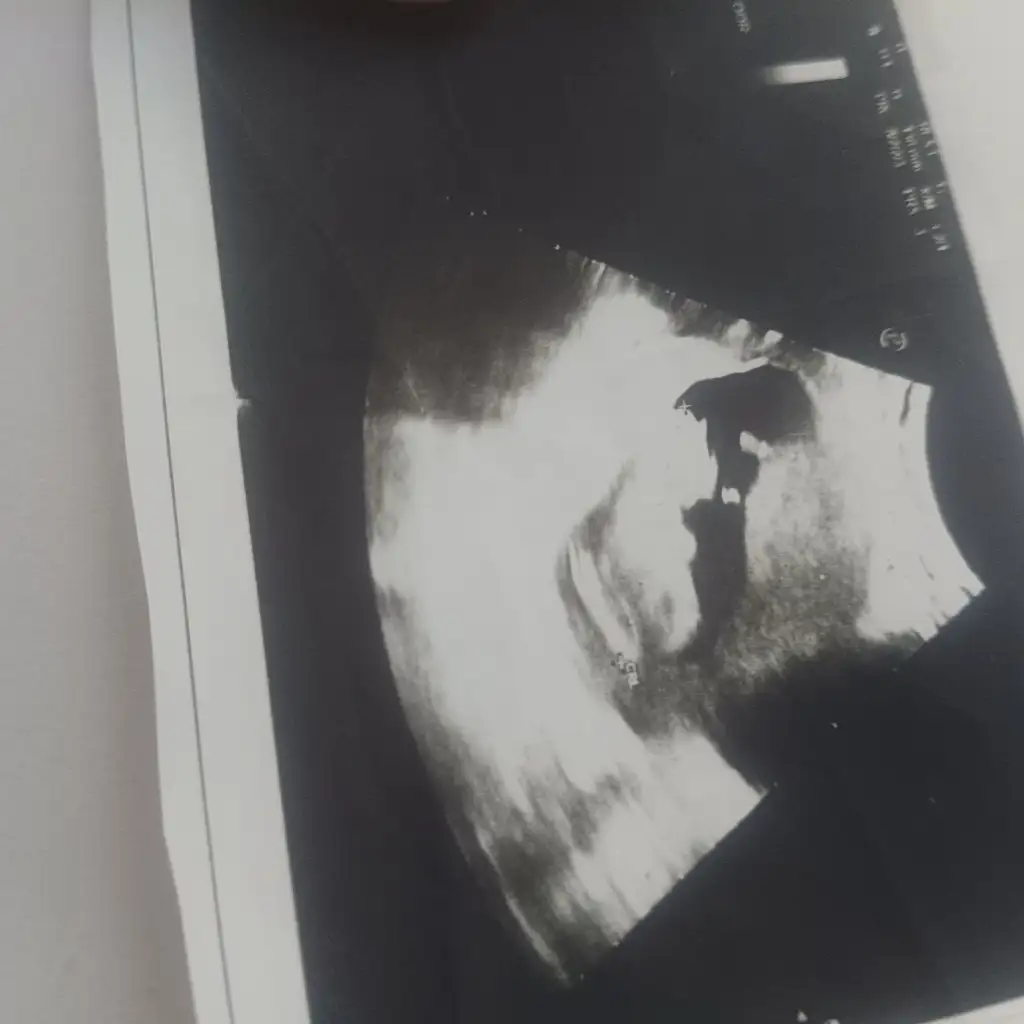

Erkek gibi geldi banadaMerhaba kızlar, benim bebişime de bir yorum yapar mısınız

Eşim erkek gibi hissediyor ben kız

ErkekMerhaba kızlar, benim bebişime de bir yorum yapar mısınız

Bana da erkek gibi geldi çabuk şekillenmiş eli kolu maşallahMerhaba kızlar, benim bebişime de bir yorum yapar mısınız

Kız güzelim :)Banada bir tahmin yaparmısınız 1 hafta ara ile farklı hastanede ultrason görüntüsü

Banada tahmin yaparmisiniz lütfenBence kız

Banada tahmin yaparmisiniz lütfen